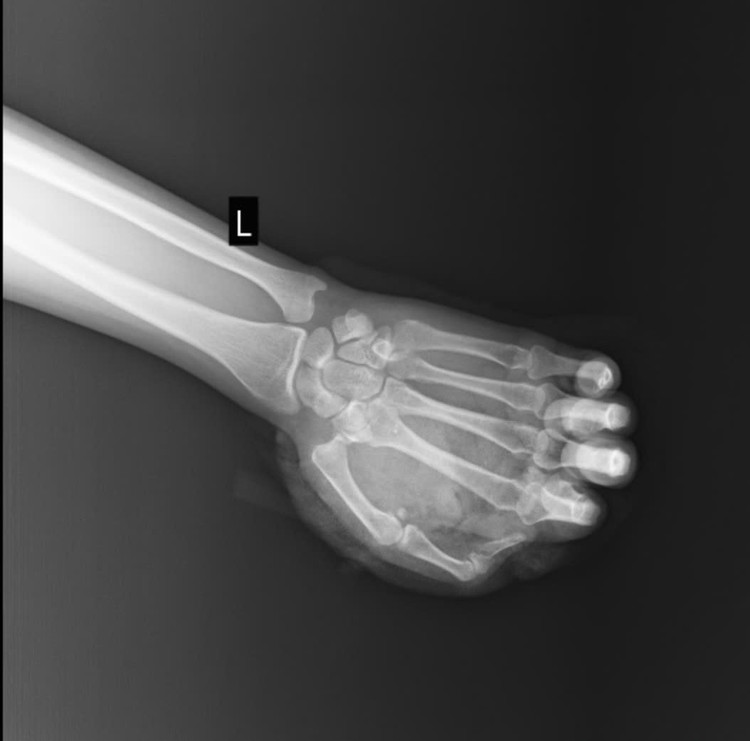

phao-no-4.jpg

phao-no-1.jpg

Tổn thương trên phim chụp - Ảnh BVCC